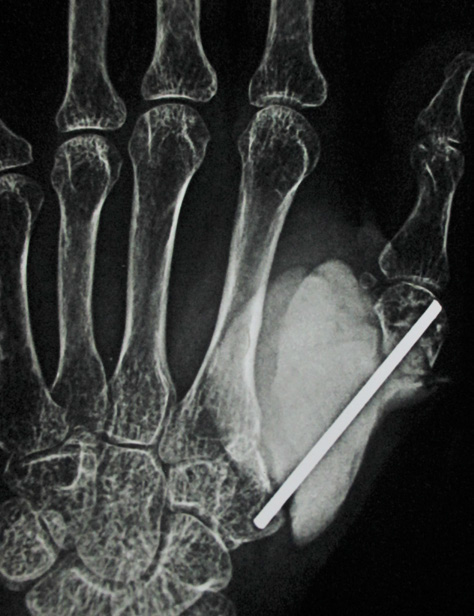

In November 2015 one 60 years lady presented in a newly recognised Medical College of eastern India (Murshidabad Medical College) with recurrence of GCT of the 1st MC of left hand and soft tissue involvement. One year back she was presented in another medical college with intraosseous Capancci grade III lesion of the same site of two years duration where it was treated with narrow margin resection, interposition bone cement on a Kirschner wire (K wire) (Figure 1). It started recurring after 8 months of resection. But presented to us after another one year when extensive extension within soft tissue took place. In plain x ray one small osteolytic lesion was noticed over mid shaft of second metacarpal of the same hand which was not seen in earlier radiographs. MRI was done to identify adjacent bone involvement and to know extent of the lesion in soft tissue (Figure 2). Involvement of regional lymph node and lung metastasis were excluded clinically and radiologically.

Figure 1 a. Initial X-ray initial presentation 3 years back; post-operative X-ray after initial operation; b. immediate; c. subsequent.

Figure 2 a. Clinical picture on presentation one year after recurrence; b. X-ray at that time showing soft tissue and second MC involvement; c & d. MRI show similar findings but without involvement of major nerve and vessels.